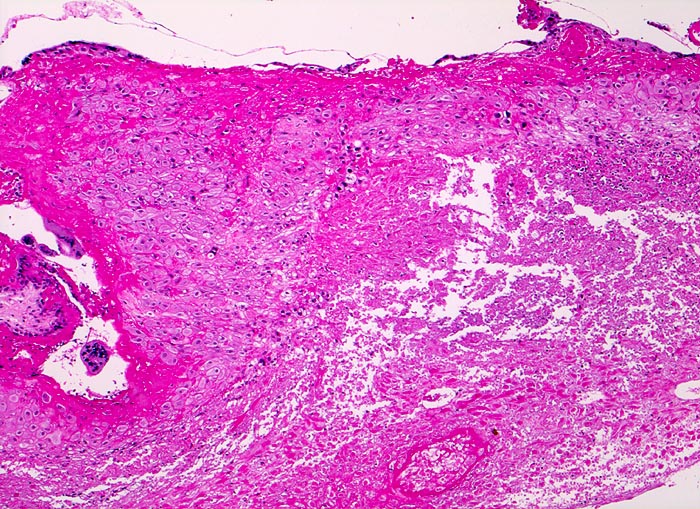

• Schwangerschaftsendometrium mit hypersekretorischen sägezahnförmigen Drüsen und bizarren Kernatypien (Arias Stella Phänomen).

Aufgabe der histologischen Untersuchung des Abortmaterials ist zum einen die Bestätigung der intrauterinen Lage der Schwangerschaft zum Ausschluss einer Extrauteringravidität. Zum anderen soll die histopathologische Untersuchung soweit als möglich zur Klärung der eigentlichen Abortursache beitragen. Vor allem müssen die therapeutisch relevanten Partialmolen und kompletten Blasenmolen histologisch diagnostiziert werden. Zwar kann die histologische Untersuchung den Verdacht auf eine chromosomale Aberration erwecken, doch ist zu deren Bestätigung eine Flowzytometrie, eine Karyotypisierung, Comparative Genomische Hypridisierung oder Fluoreszenz in Situ Hybridisierung erforderlich und sinnvoll. Der Verdacht auf eine Koagulopathie soll zur Abklärung der mütterlichen Gerinnungsparameter führen. Am Paraffinmaterial ist der gezielte Nachweis einer Mutation möglich, z.B. von Faktor V Leiden.